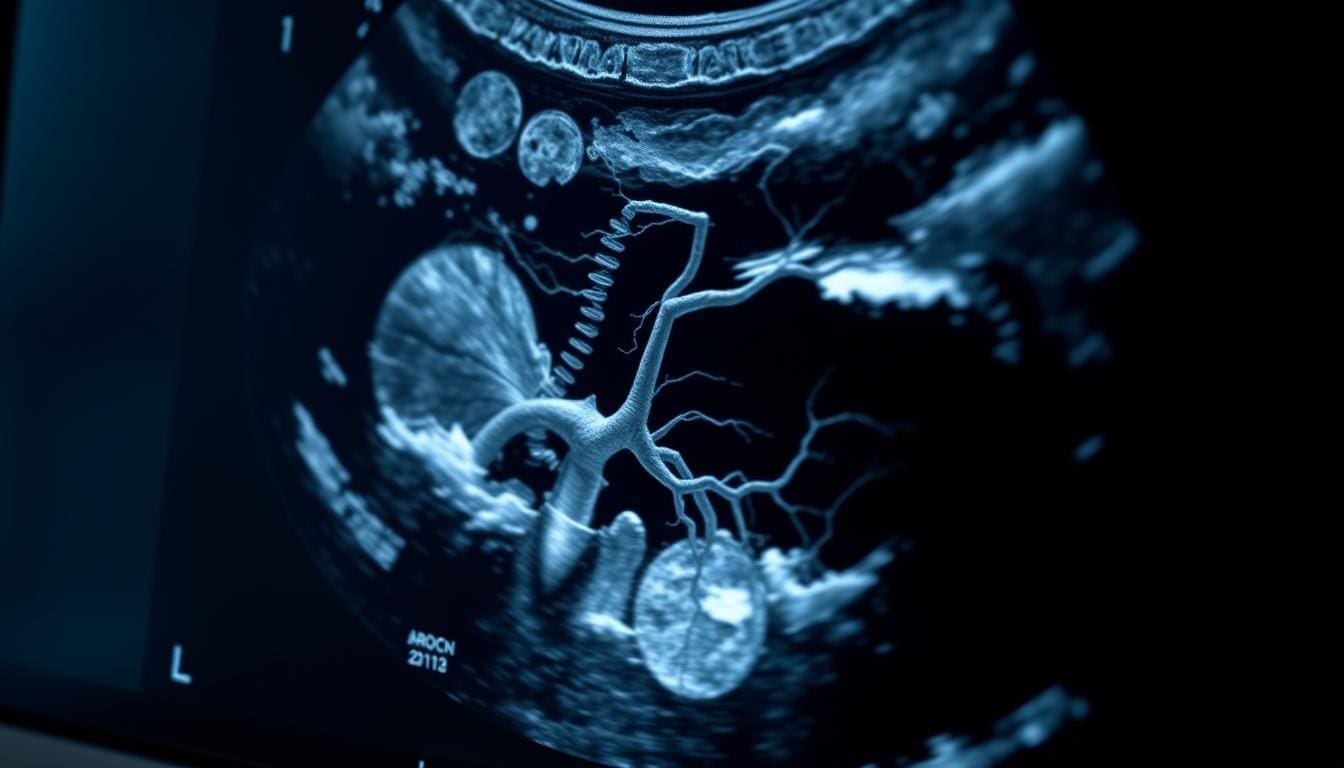

IR in Medical Context: Interventional Radiology Explained

Interventional radiology is changing healthcare with new, image-guided treatments. It’s a medical field that uses imaging to do procedures without invasive surgery. This makes treatments safer and less invasive for patients.

Definition and Scope of Interventional Radiology

Interventional radiology uses images to guide treatments. It treats many conditions like vascular diseases and cancer. Healthcare professionals use IR for precise treatments that heal faster and with fewer risks.

Imaging Technologies Used in Interventional Radiology

The success of IR procedures depends on advanced imaging technologies. We use different imaging modalities for our interventions, including:

- Fluoroscopy: Gives real-time X-ray images.

- Ultrasound: Uses sound waves for body images.

- Computed Tomography (CT): Offers detailed cross-sectional images.

- Magnetic Resonance Imaging (MRI): Provides high-resolution images without radiation.

These imaging technologies help us perform complex procedures safely and precisely. The combination of advanced imaging with IR procedures has greatly contributed to the growth of Interventional Radiology.